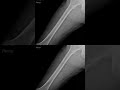

الفخذ اشعة ديجيتال تصوير وضعية الفخذ